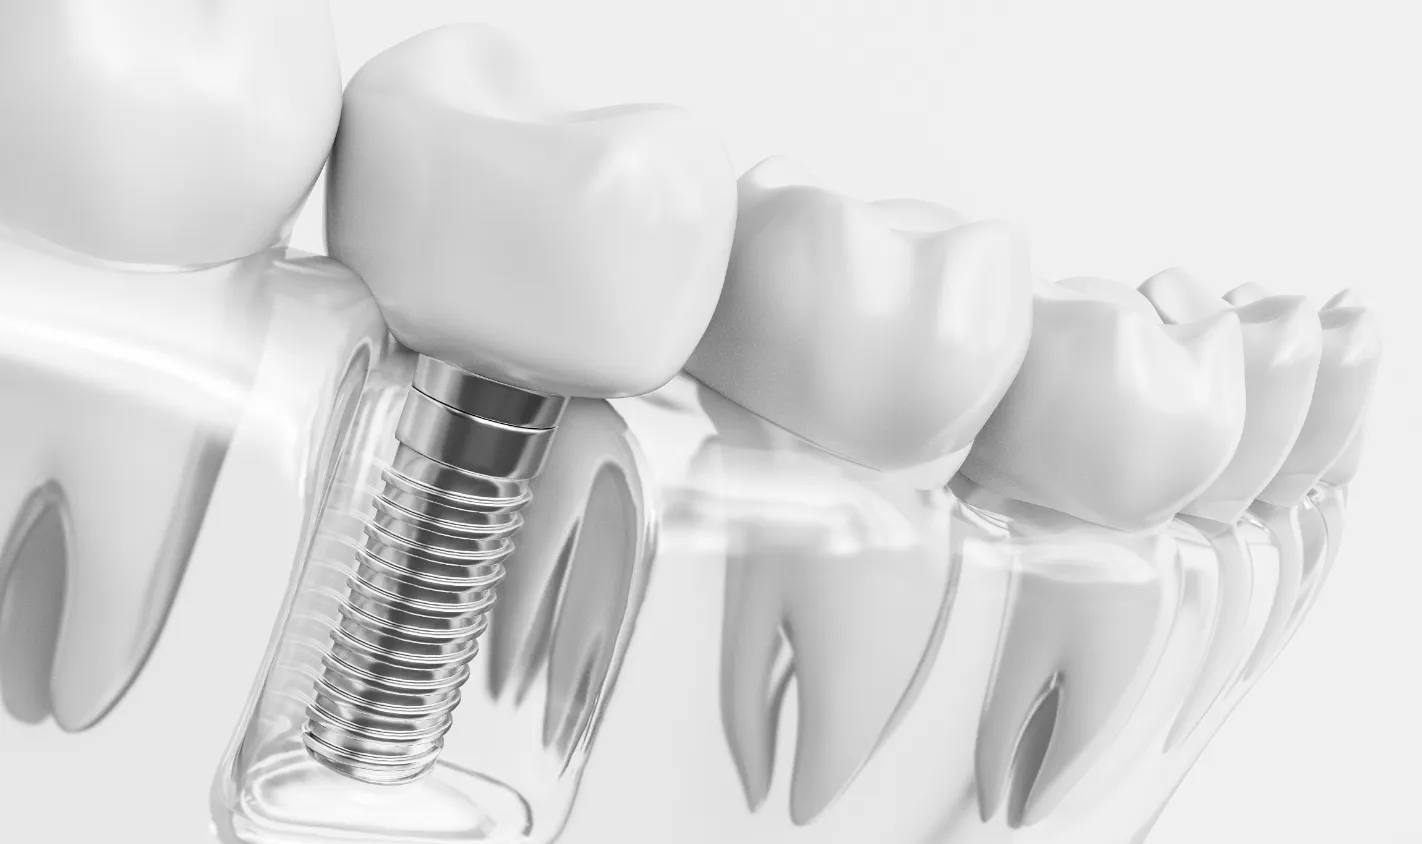

インプラント治療

失った歯を補う方法の1つで、インプラントが歯根の代わりを果たすことで天然歯に近い噛み心地を再現します。当院ではサージカルガイドを使用することで、より精密な埋入を可能とし、術後の痛みや腫れを軽減しています。機能性だけでなく審美性も回復します。